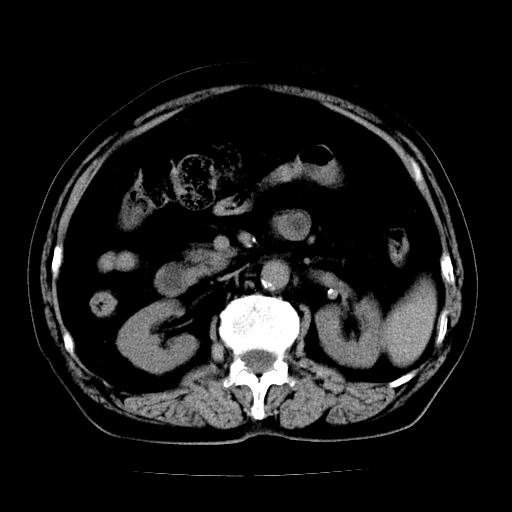

男,71岁,皮肤黄染四天。

肝内外胆管及胆总管上段扩张,考虑为梗阻所致,建议mrcp检查。

考虑胆总管癌并肝内外胆管扩张。

胰腺上端胆总管内见软组织影,强化不明显,结合临床,还是考虑低位梗阻性黄疸,胆总管癌可能性大